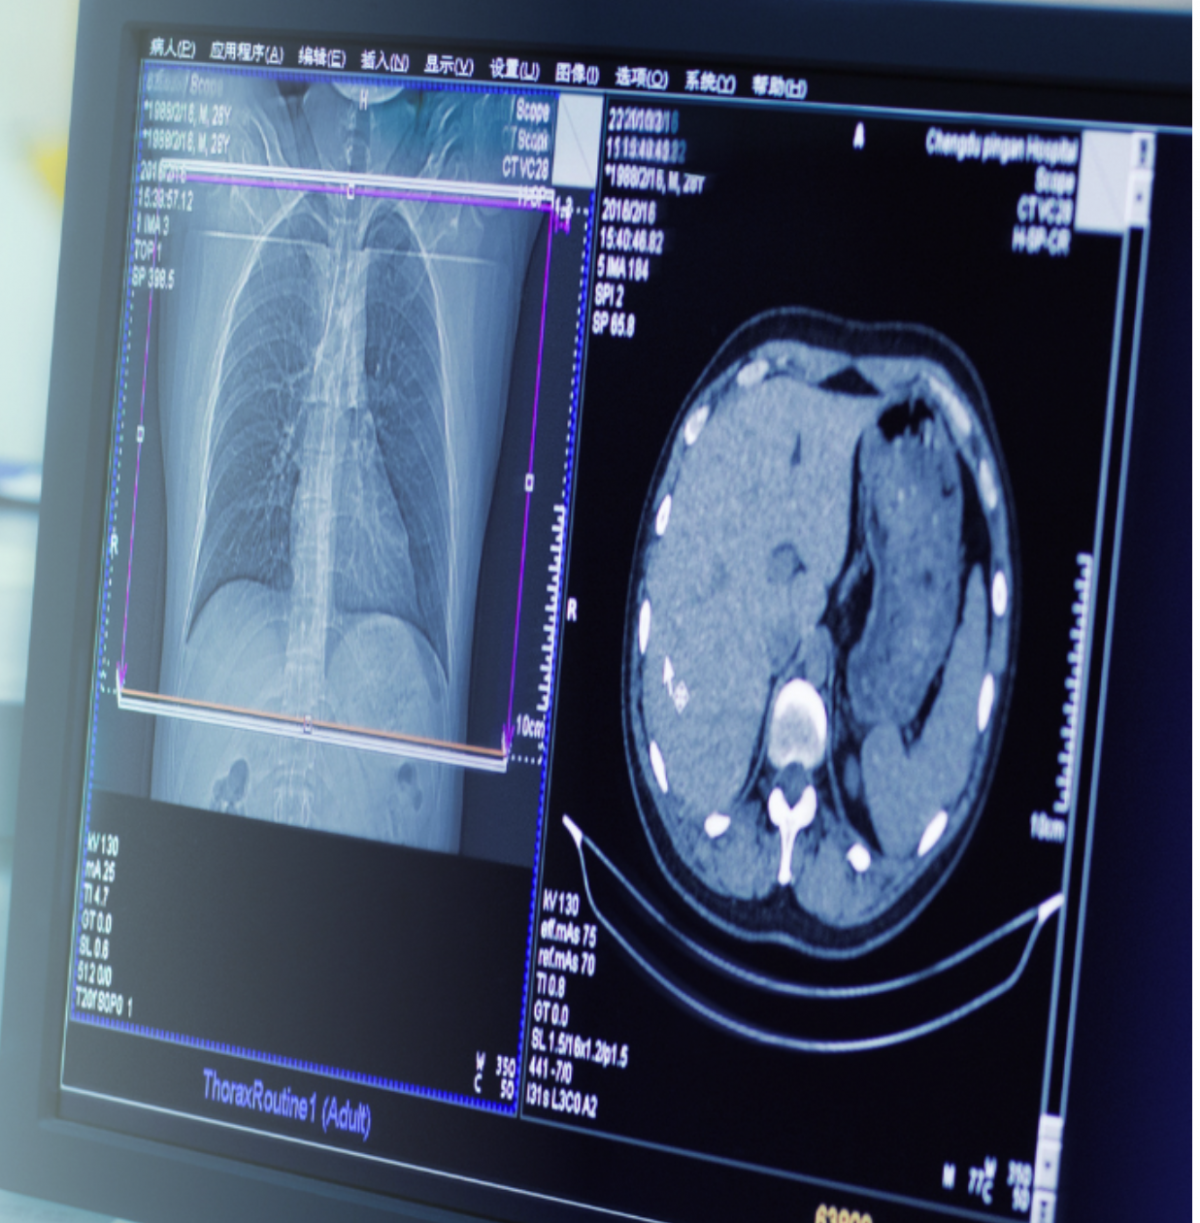

Вже можна записуватись на безоплатну комп’ютерну томографію в онкоцентр

— Він дійсно в нас був поламаний з грудня місяця, але з минулої п’ятниці вже працює, — говорить Сергій Перегончук. — Тобто сьогодні/завтра пацієнт може зателефонувати до нашого кол-центру і записатися на проходження обстеження. Безоплатним це обстеження для пацієнтів буде, якщо є направлення сімейного або лікуючого лікаря.

— В нашому онкоцентрі цей апарат один, але ми плануємо цього року закупити другий КТ, — говорить Сергій Перегончук.

— Нам вдалося за підсумками 2023 року черги зменшити до трьох-чотирьох місяців, але через зламаний КТ, два з половиною робочих місяці в нас випало, і черга знову стала більше, — каже головний лікар. — Та ми працюємо над тим, щоб її оптимізувати. Наш центр проводить обстеження тільки з внутрішньовенним контрастуванням. І залежно від того, скільки записано пацієнтів, в кабінеті комп’ютерної томографії вже попередньо підготовлено. Тож кожен пацієнт, який має прийти на свій час — одразу без затримки обстежується.